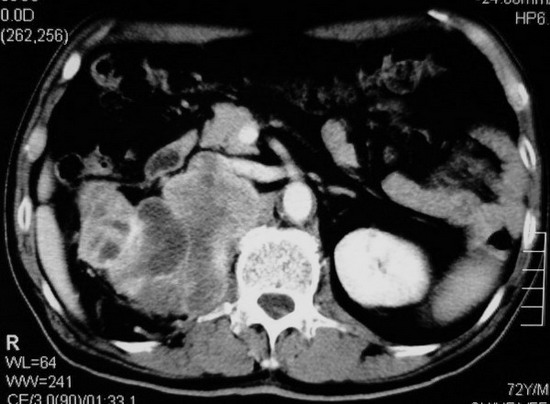

以下是引用杀毒软件在2008-11-17 19:15:00的发言:[br]考虑------右肾癌合并肾静脉---同侧肾上腺受侵可能性大

以下是引用zjzjr在2008-11-17 20:45:00的发言:[br]考虑------右肾癌合并肾静脉---同侧肾上腺受侵可能性大及腹膜后淋巴结转移.